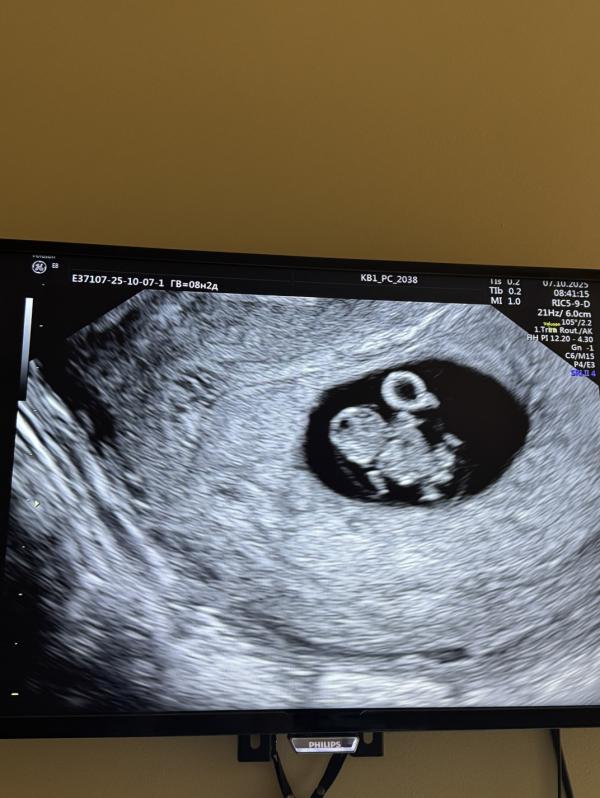

На узи все хорошо , сердце бьется . В 8.5 недель еще узи , там уже видны крошечные очертания пупсика , сердце бьется все хорошо .

Но видимо не суждено было. Молчание , переспрашивает срок , говорит маленький размер … включает сердцебиение , а там тишина 🔇 и слова сердце не бьется так бывает . Замер на 9,5 недель .